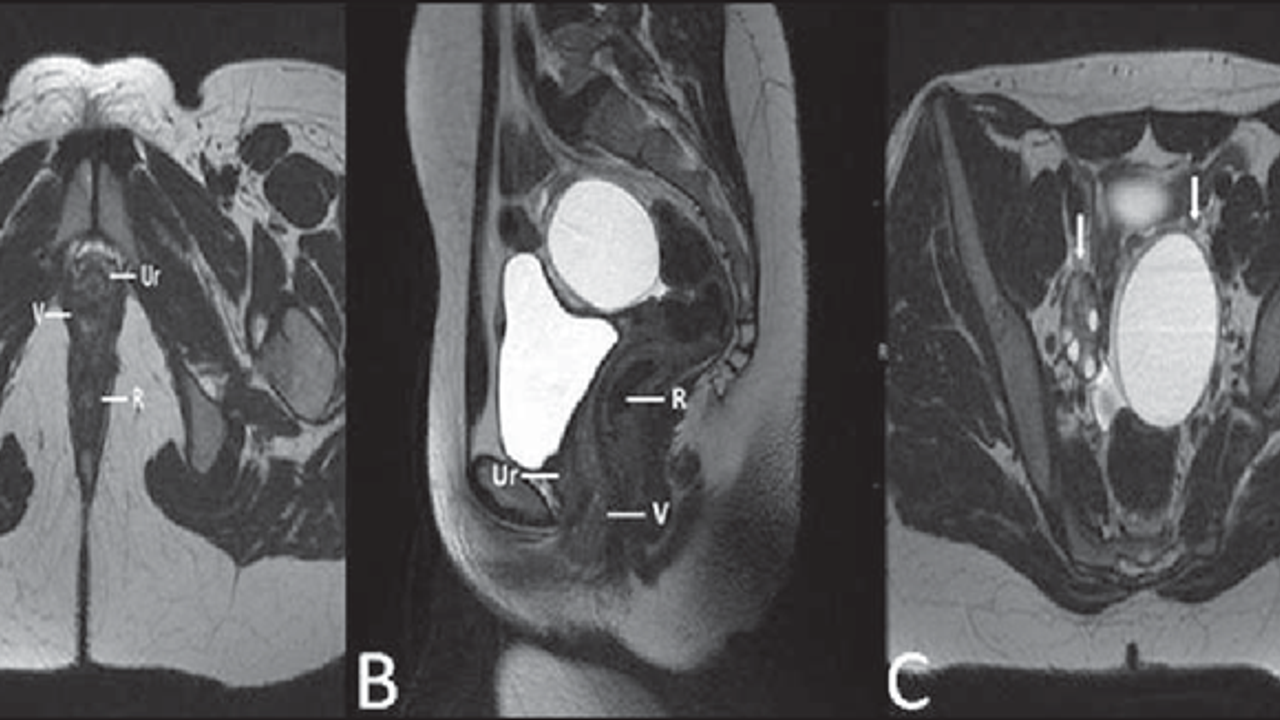

"Hastamızın rahmi ve vajinası bulunmamaktaydı. Ayrıca böbrek anomalileri de vardı. Kendi karın zarını kullanarak vajina oluşturduk. Şu anda genel durumu çok iyi, kontrolleri de olumlu gidiyor," dedi.

"Dış genital organlarda ve göğüs gelişiminde problem görülmez. Ancak rahim ve vajina gelişimi yoktur. Bu durum ancak detaylı muayene ve görüntüleme ile fark edilir," açıklamasında bulundu.